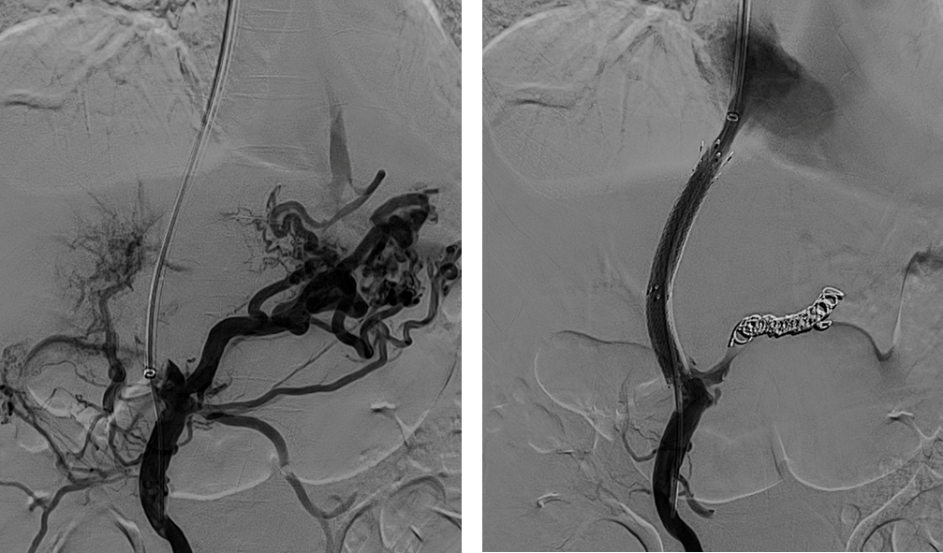

图3. TIPS治疗阻塞性PVT伴静脉曲张出血病例展示